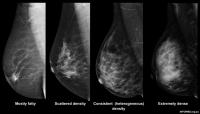

image: Researchers say chronic low-level inflammation drives increased breast density. view more

Almost 8% of women have extremely high breast density and are more likely to develop breast cancer in the future.